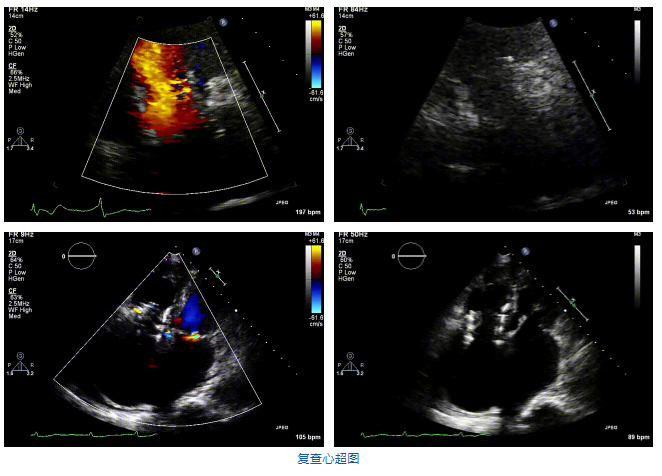

2021年12月7日,復(fù)旦大學(xué)附屬中山醫(yī)院葛均波院士團(tuán)隊(duì)完成的首批兩例LuX-Valve Plus經(jīng)血管三尖瓣置換患者順利出院,從患者入院至出院僅歷時(shí)一周時(shí)間,出院時(shí)患者狀態(tài)恢復(fù)良好,復(fù)查心超三尖瓣無反流。

結(jié)合術(shù)前CT評(píng)估結(jié)果,葛均波院士團(tuán)隊(duì)最終決定選用LuX-Valve Plus 50mm和55mm兩種型號(hào)的瓣膜,并于2021年11月30日順利完成LuX-Valve Plus經(jīng)血管三尖瓣置換術(shù),手術(shù)室即刻拔除氣管插管,術(shù)后第二天轉(zhuǎn)出心內(nèi)科監(jiān)護(hù)室,下床活動(dòng)。術(shù)后患者三尖瓣反流癥狀得到顯著改善,復(fù)查心超結(jié)果顯示人工三尖瓣瓣膜支架固定穩(wěn)定,瓣葉關(guān)閉形態(tài)未見異常,未見明顯反流。

在本次救治性臨床研究中,治療的兩例患者病因不同,解剖結(jié)構(gòu)復(fù)雜,均為極重度三尖瓣反流,手術(shù)最終都順利植入了LuX-Valve Plus三尖瓣人工瓣膜。術(shù)后超聲顯示瓣膜支架固定穩(wěn)定,反流癥狀顯著改善,取得了良好臨床治療效果。